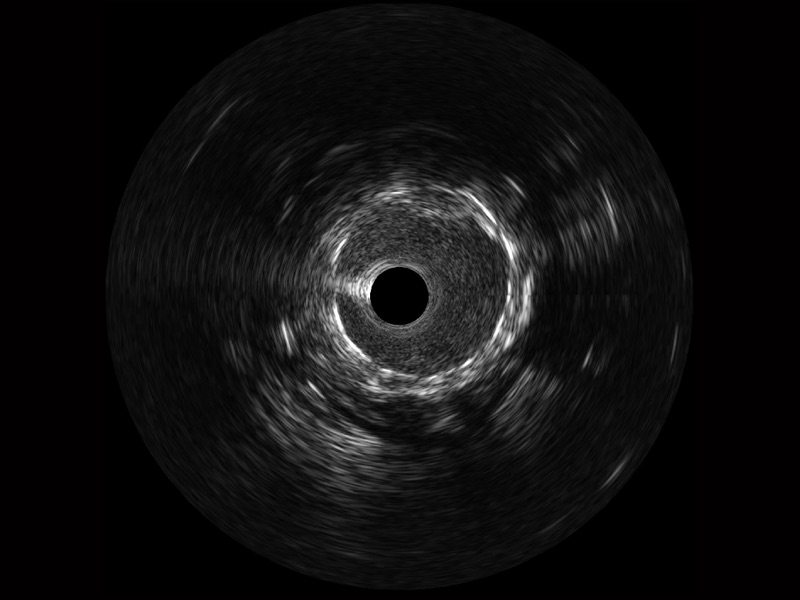

MILE米乐集团官网宽频IVUS图像

对比传统IVUS导管成像,MILE米乐集团官网宽频IVUS图像的近场支架梁显影更细腻,远场中膜外血管仍清晰可辨,兼顾远中近,兼顾分辨力与穿透深度